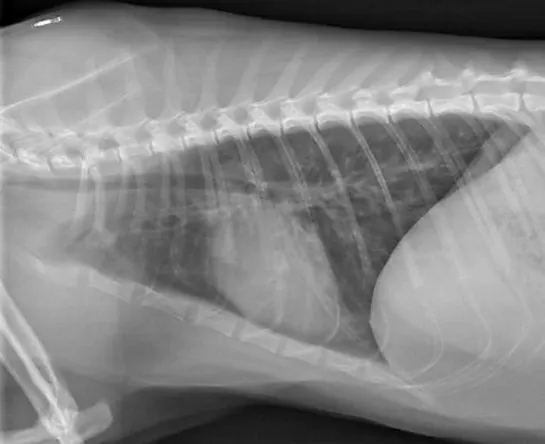

Allergic airway disease can result in restriction of the lower airways (ie, bronchi); the most common form is feline asthma.8 Patients with lower airway obstruction typically exhibit tachypnea with expiratory distress (ie, prolonged expiration), coughing, or wheezes; radiographs will indicate a bronchial pattern (Figure 2).

Featured Image

FIGURE 2

Lateral thoracic radiograph of a cat with severe asthma demonstrating a bronchial pattern characterized by “railway tracks,” “doughnuts,” and hyperinflated lungs

Patients with allergic airway disease can benefit from oxygen and sedation as outlined here for upper airway obstructions. Concurrent administration of an inhalant (eg, albuterol [1-2 puffs q30-60min]) or injectable bronchodilators (eg, terbutaline [0.01-0.05 mg/kg IV/IM/SC] q4-12h) is recommended. In addition, injectable, oral, or inhaled anti-inflammatory doses of corticosteroids are recommended to help reduce small airway inflammation and prevent fibrosis.8